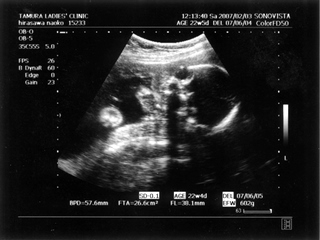

アクセス解析				 | × [PR]上記の広告は3ヶ月以上新規記事投稿のないブログに表示されています。新しい記事を書く事で広告が消えます。 5ヶ月(18週と5日) 体重:262g BPD(頭を上から見た耳から耳の幅のような感じ):46.8㎜ FTA(お腹の断面):15.9平方㎝ FL(大腿骨長 太ももの骨の長さ):22.7㎜ 6ヶ月(22週と5日) 体重:602g BPD(児頭大横径 頭を上から見た耳から耳の幅のような感じ):57.6㎜ FTA(体幹横断面 お腹の断面):26.6平方㎝ FL(大腿骨長 太ももの骨の長さ):38.1㎜ まだこの頃は顔と上半身が収まっていました。 検診は妊娠23週までは、4週に一度なのでドキドキとワクワクです。 ちゃんと成長してるかなあなんて考えて行って、 心音をきいたり、エコーを見て毎回安心と喜びがわいてきます(*^_^*) たった4週で、体重は3倍近くにも!かわいいなあ☆ 6ヶ月の検診日ダンナっちは仕事だったから、 エコー写真を携帯で撮って送ると、 『目ん玉でてない!?』 と返事が返ってきました。 眼球がそう見えるんだろうけど、目のとても細いダンナっちには 衝撃的だったんですね(^。^;) 胎動を初めて感じた日をわたしはわかりません・・・ メモにとるなり、日記にかくなりすることをすっかり忘れてしまって、 今となって後悔<<o(>_<)o>> ダメな母親めっ と思いつつも、わたしらしいと感じ笑っています(^_^;) 12月の末に友達に、 「腸の動きか!?って思うのはあるんだけどまだよくわかんない」 と言ったのを覚えているので、12月の終わりから1月にかけての あたりなんでしょうね。 いつの間にかポッコポッコしていました! ベイビーこんなママだけどよろしく└|∵|┐♪┌|∵|┘ 6ヶ月までは、普通にそれまで履いていたジーンズも入っていたんだけど、 6ヶ月終わるころには、急に入らなくなってビックリしました~ 食生活の変化も特になかったです。 あ、ポテトチップスあまり自分で 買わなかったのに、1週間くらいブームの時期がありました!妊娠による影響かな!? PR この記事にコメントする